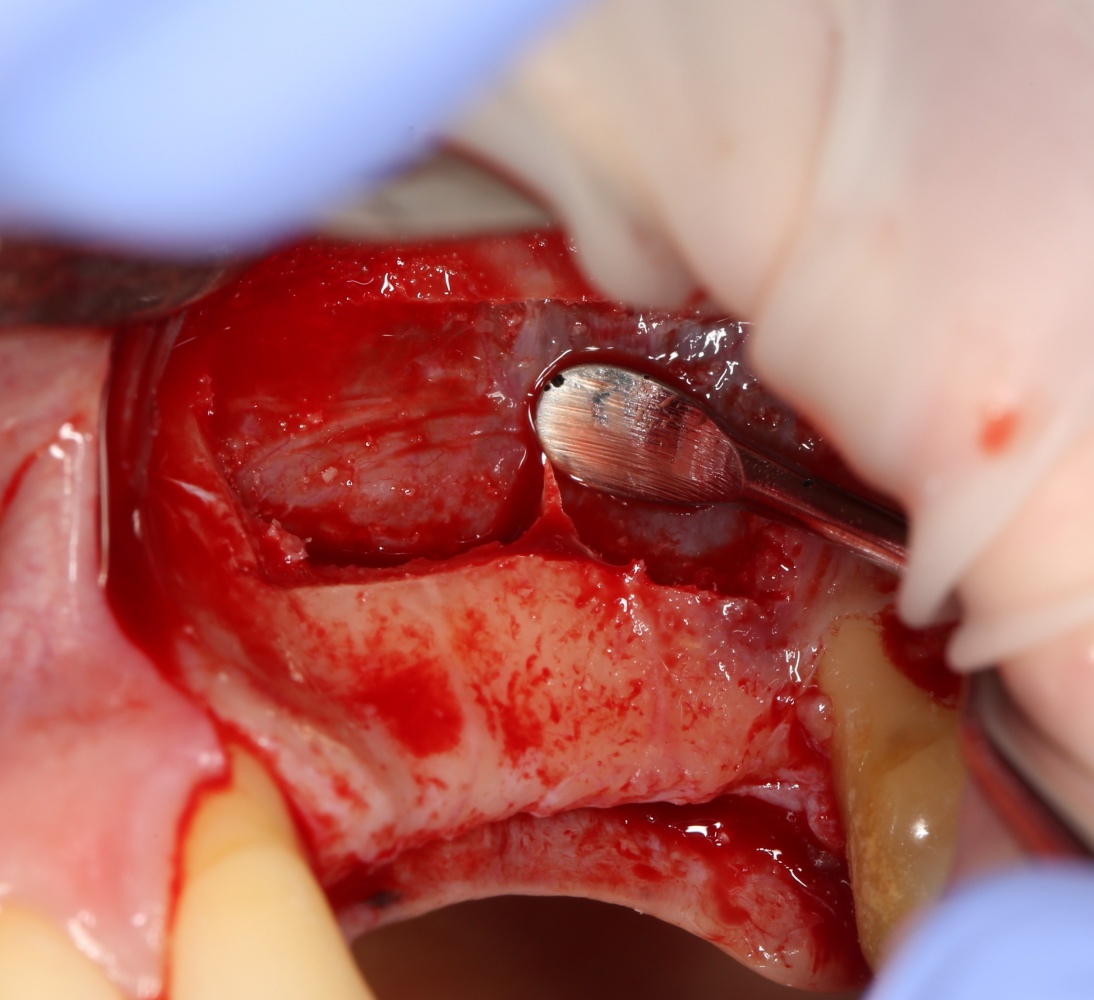

Кстати, обрати внимание на ширину альвеолярного гребня (левая картинка). Она чуть меньше 3 мм. Это объясняет, почему я засомневался в возможности установки имплантатов одновременно с остеопластикой. Понятно и без КЛКТ.

Наперво, мне нужно удалить разрушенный зуб и получить костный аутотрансплантат.

Для получения костного блока, мы открываем донорскую зону, наружную косую линию нижней челюсти.

Получение костного аутотрансплантата.

Здесь потребуется пародонтологический зонд с миллиметровой разметкой или какой-то другой измерительный прибор (операционная линейка). Ранее по КЛКТ я измерил костный дефект, теперь нужно нанести границы будущего костного блока на донорскую зону.

Ремарка: некоторые доктора предлагают делать хирургические шаблоны или выкройки специально для точного забора костного блока. На мой взгляд, это чрезмерное усложнение - во-первых, использование подобных шаблонов или выкроек требует увеличения площади раны, во-вторых, это увеличивает время и стоимость лечения, в-третьих, на этом этапе не требуется высокая точность, поскольку блок всё равно потребует адаптации.

Иными словами, важна не точность, а быстрый, аккуратный и, что главное, малотравматичный забор аутотрансплантата.

Для получения костного блока мы использовали ультразвуковую пьезохирургическую систему. Это самый удобный и безопасный инструмент для проведения подобных манипуляций. С помощью него мы сформировали и выделили костный блок. Он должен отделяться легким движением остеотома или элеватора. Как это сделать правильно — читай здесь>>

Кстати, если костный блок не отделяется от костного ложа легким движением элеватора, значит он неправильно сформирован или не до конца выделен. Вообще, любое чрезмерное усилие в хирургии — это всегда следствие рукожопия. Если тебе что-то приходится делать с усилием (установка имплантата, удаление зуба и т. д.) — значит ты делаешь это неправильно. Остановись и подумай, что именно.